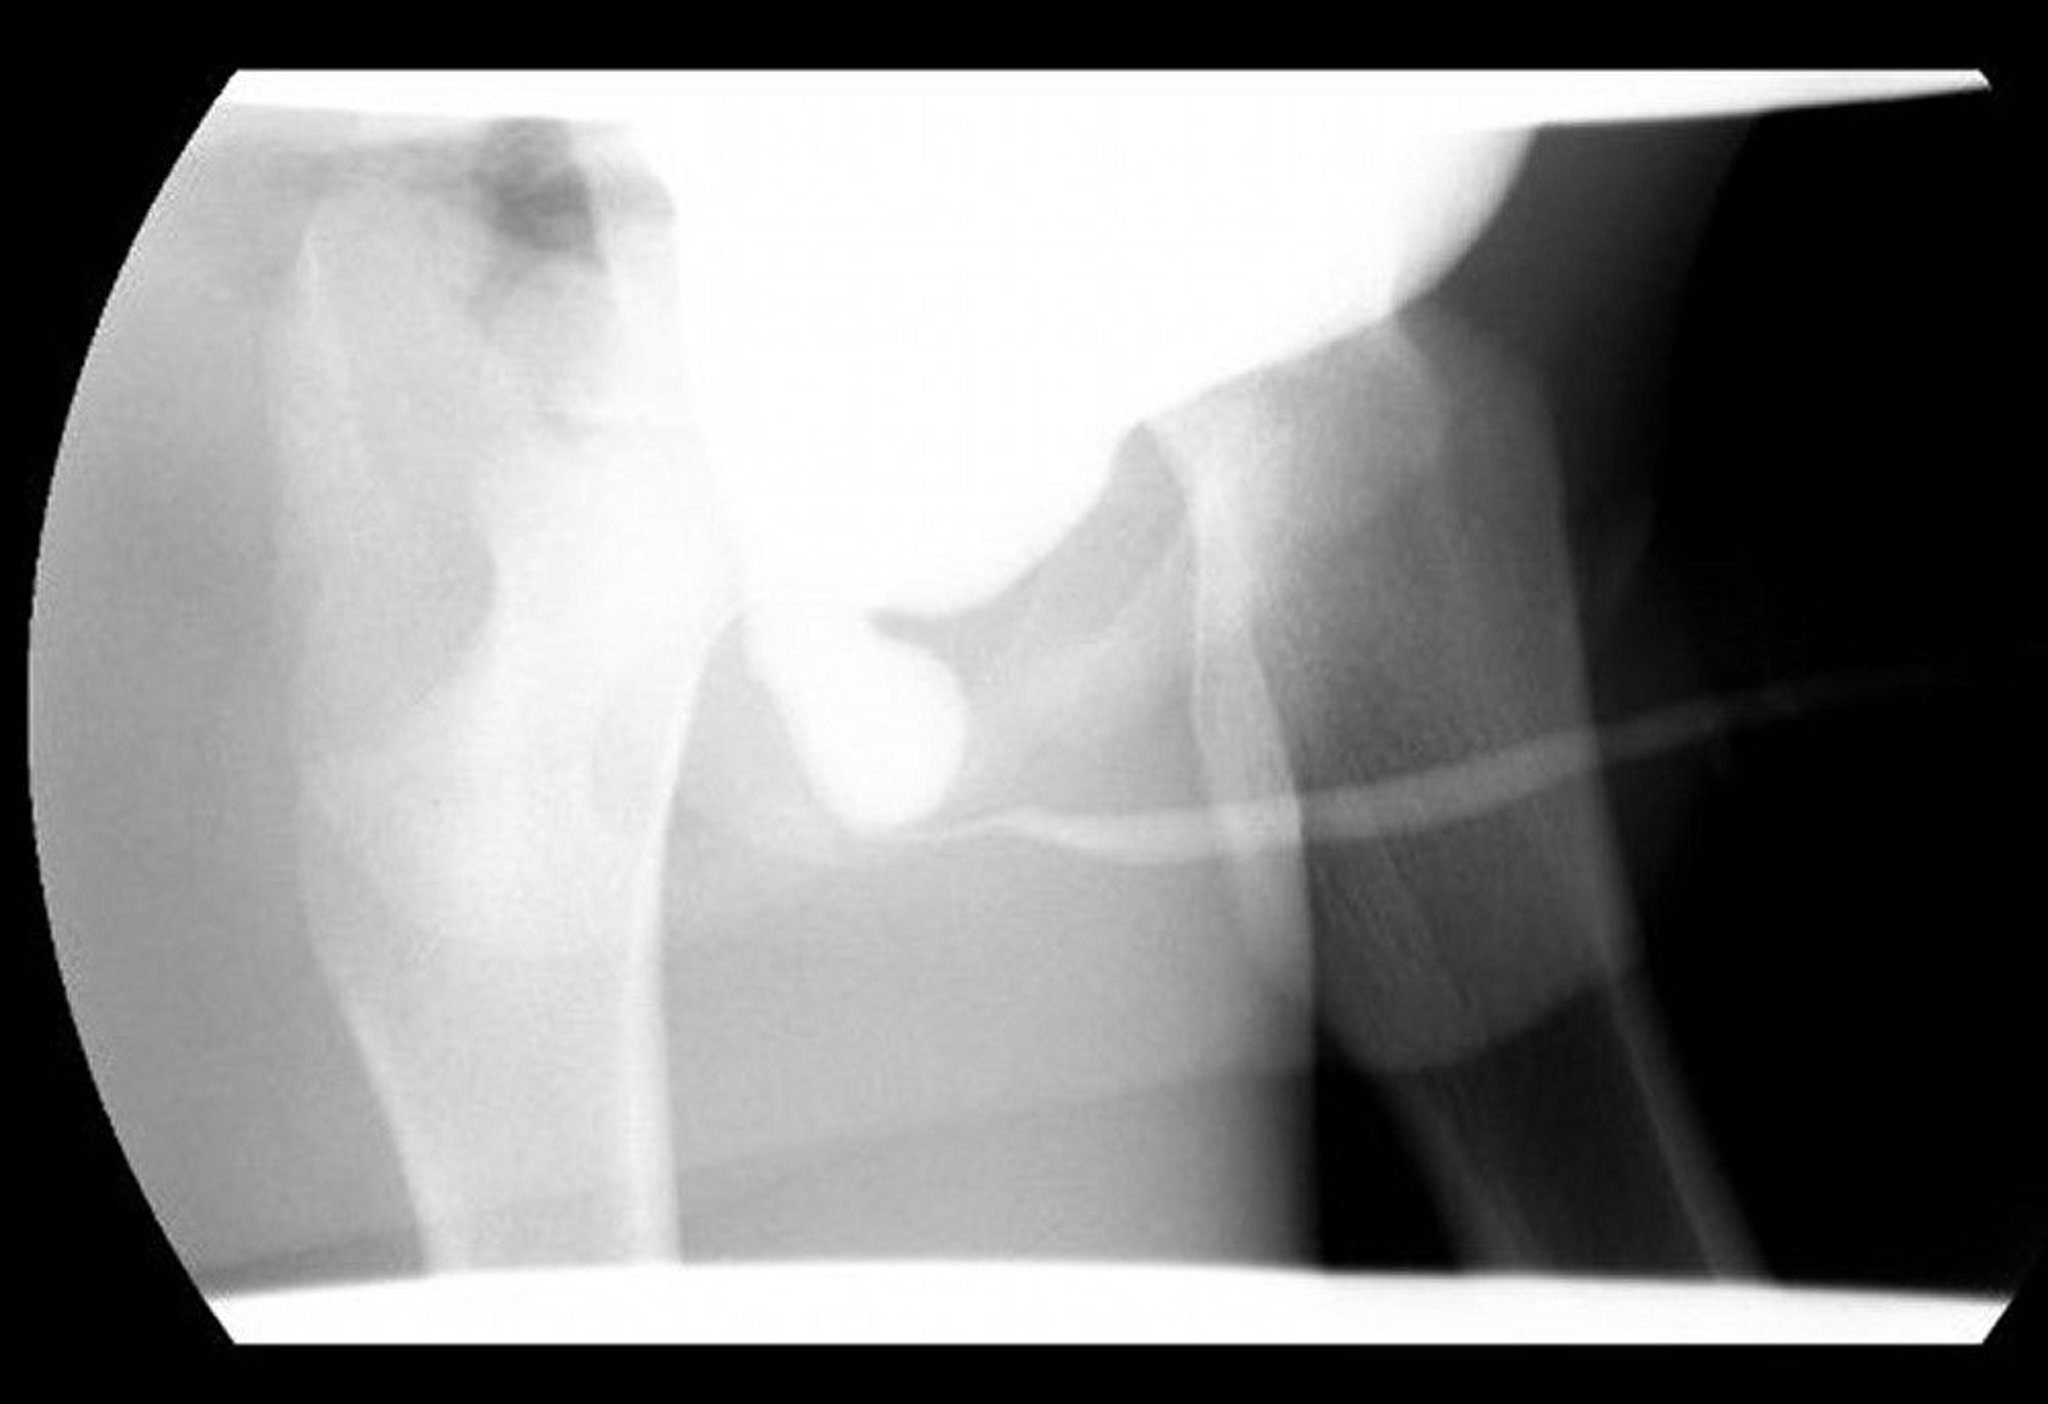

Esta imagen de cistouretrografía miccional (CUGM) muestra una uretra posterior dilatada con obstrucción distal debido a válvulas uretrales posteriores.

Image courtesy of Drs. Ronald Rabinowitz y Jimena Cubillos.